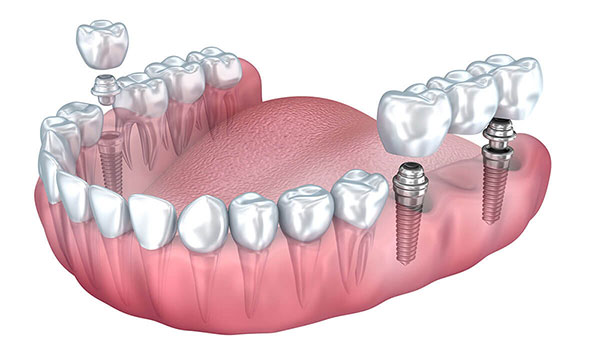

۲. استفاده از پل متکی بر ایمپلنت (روش ترکیبی)

روش دوم که امروزه رایجتر و مقرونبهصرفهتر است، استفاده از پل متکی بر ایمپلنت است. در این حالت برای جایگزینی چند دندان متوالی به جای کاشت ایمپلنت برای هر دندان، تعداد کمتری پایه ایمپلنت قرار داده میشود. به طور مثال، دو ایمپلنت میتوانند سه یا حتی چهار دندان از دست رفته را پشتیبانی کنند. در این روش پروتز یا بریج ساختهشده روی اباتمنتهای ایمپلنت نصب میشود و جای خالی دندانها بهطور کامل پر میگردد.

- برای هر دندان یک ایمپلنت گذاشته نمیشود.

- بلکه به طور مثال با ۲ ایمپلنت، ۳ یا ۴ دندان متوالی جایگزین میشوند.

۵. نصب اباتمنت: بعد از جوش خوردن پایهها، قطعهای به نام اباتمنت (Abutment) روی ایمپلنت قرار میگیرد. اباتمنت رابط بین پایه و تاج دندانی است.

۶. ساخت و نصب پروتز (تاج یا بریج): در نهایت، پروتزهای دندانی (تکتک یا پل متصل) ساخته شده و روی اباتمنتها قرار میگیرند. این پروتزها کاملاً شبیه دندان طبیعی طراحی میشوند تا: